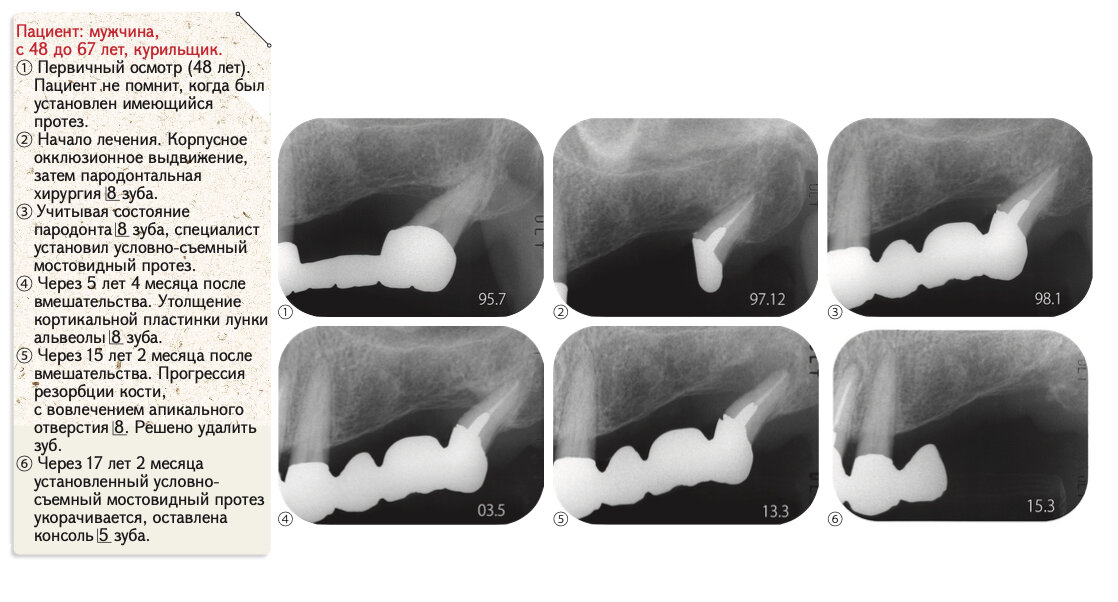

Рис. 2. Условно-съемный мостовидный протез, установленный в данном случае

Клинический опыт приобретается при лечении сложных случаев, в данной ситуации их предостаточно (рис. 2). Через 5 лет после лечения определяется временная стабилизация состояния пародонта зуба мудрости. Со временем, в результате функциональной нагрузки, кортикальная пластинка лунки альвеолы утолщается, наблюдается прогрессия пародонтита. Примерно через 15 лет зуб удаляется. Здесь приведен клинический случай длительного сохранения зуба при спорной тактике лечения, которую сам лечащий доктор вряд ли назовет правильной.

Рис. 1, 2 демонстрируют применение молодым неопытным специалистом «условно- съемного мостовидного протеза» при лечении пациента с частичными дефектами зубных рядов. Действительно, часто выбор тактики лечения при различных клинических ситуациях основывается исключительно на личном опыте практикующего доктора и технических возможностях клиники. Решение единолично принимается в «секретной комнате», за закрытыми дверями. Личный опыт, а не общепринятые стандарты качества становятся эталоном и ориентиром во всех ситуациях, будь то длительность отверждения фотополимерного материала, форма культи отпрепарированного зуба или оценка качества полученного оттиска.